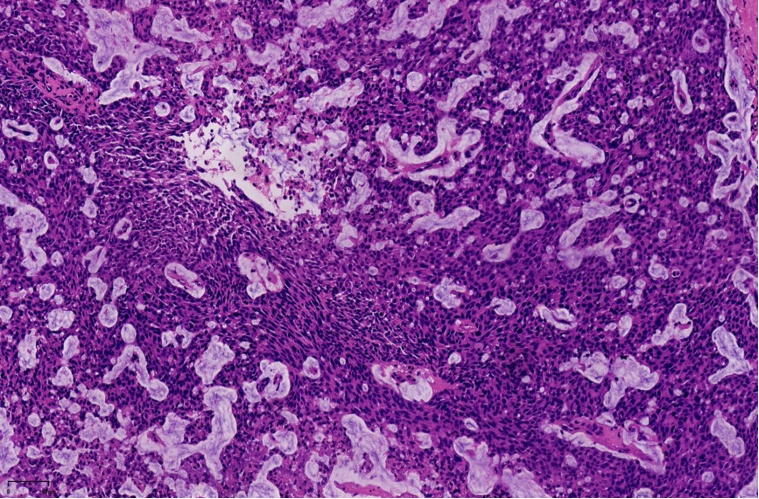

实性乳头状癌(原位或浸润)是一种以纤细血管纤维轴心和实性生长模式为特征的肿瘤,常有神经内分泌分化,生物学行为为惰性。

结构特点:轮廓清楚的实性结节纤细的血管轴心。

纤细的脉管轴心

纤细的血管轴心周围细胞呈栅栏状排列

特征性细胞:形态多样,卵圆形,梭形,多边形,印戒样或浆细胞样胞浆嗜酸性颗粒状,单形性,核低至中级别,染色细腻,可见小核仁核分裂少见(<5/10HPF)肿瘤细胞可有细胞内、外粘液形态单一,呈圆/卵圆形,胞浆淡染、嗜酸性颗粒状嗜酸性颗粒状

细胞内外粘液,可以在细胞与纤维轴心之间,也可在细胞与导管壁之间细胞外黏液

1、浸润性实性乳头状癌:保留实性乳头状结构,体积大的团巢,轮廓不规则,间质促纤维反应,肌上皮缺失,原位SPC背景

2、实性乳头状癌伴浸润:轮廓圆滑的结节,伴有浸润性成分,包括粘液癌,NET,浸润性癌(NST)

SPC+富于细胞的黏液癌